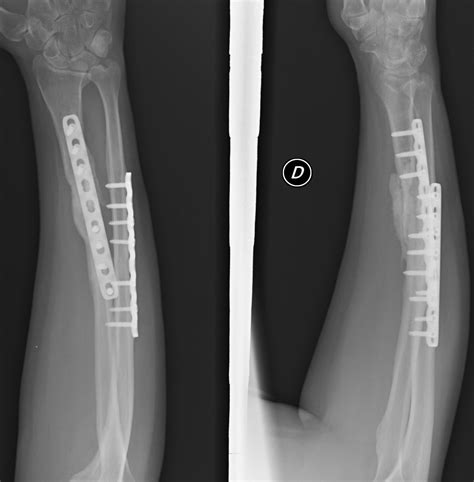

Surgical Treatment

For more severe fractures, surgery may be necessary. Surgical options include:

• Open Reduction and Internal Fixation (ORIF): This procedure involves realigning the broken bones and securing them with plates, screws, or rods.

• External Fixation: In some cases, an external fixator may be used to stabilize the bones from outside the body.